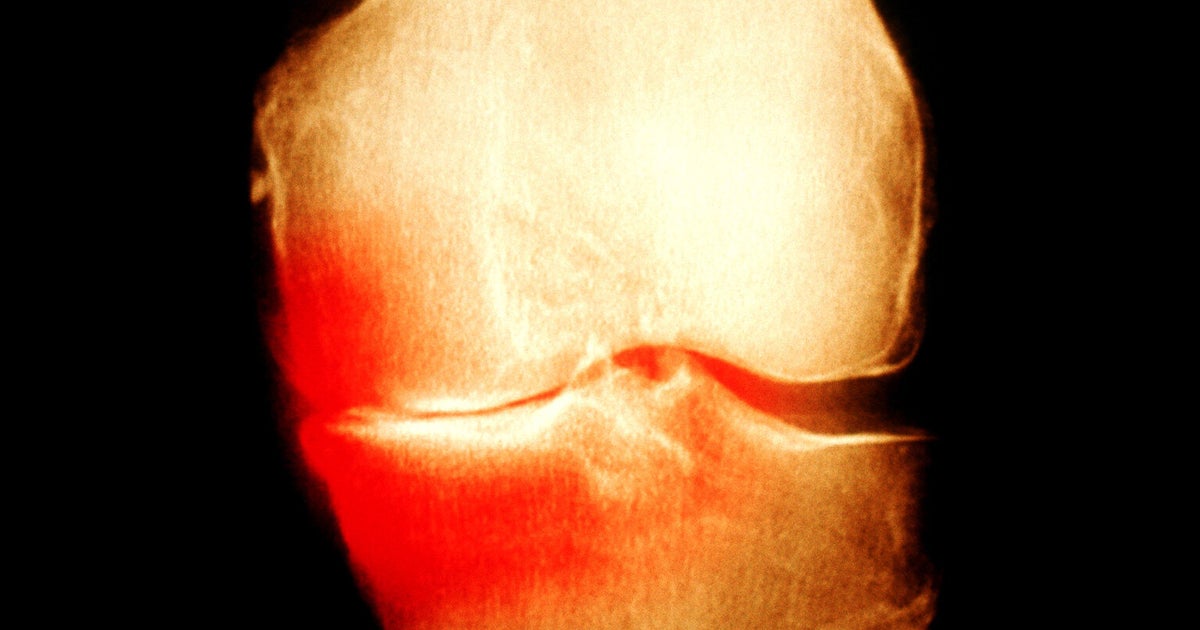

From www.sportsmedreview.com

Diagnosing Osteoarthritis with Knee Radiograph Sports Medicine Review Osteoarthritis Sports Injuries osteoarthritis (oa) is one of the most devastating chronic conditions. we found that collectively participation in the sports in this review. Without that slippery, smooth shock. osteoarthritis is a type of arthritis that happens when cartilage in your joints wears down. Injuries, such as those that occur when playing sports or from an accident, can increase the. Osteoarthritis Sports Injuries.